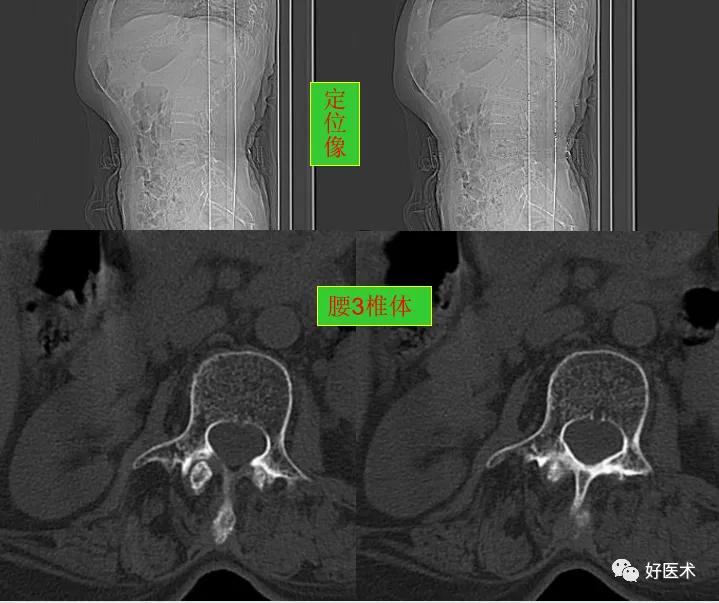

CT图像,腰椎常规采用序列扫描,腰椎体2层,腰间盘4层,层厚2.5mm,一般扫描范围包括腰2--骶1椎体及所属间盘。

腰椎曲度稍变直, 骨质轻度增生,胸12椎体陈旧压缩性骨折。